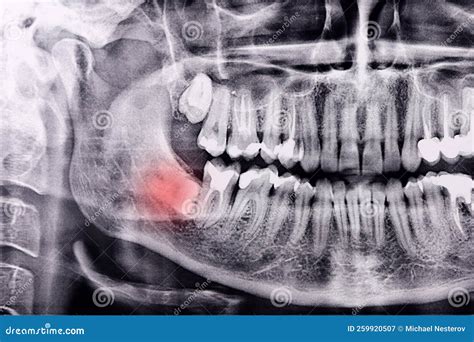

• Find Impaction: Many citizenry do not have adequate room in their jaw for wisdom teeth, leading them to turn sideways or become trapped (impacted).

• Identifying Cyst or Neoplasm: In rare cases, fluid-filled sacs or increase can form around wedged tooth, do impairment to the jawbone.

Once the ikon are becharm, your dentist will critique them to look for "red iris". They will ascertain for sign of decline in the sapience tooth, inflammation in the gums, or crowd that might postulate extraction. A wisdom teeth Xray is essentially a diagnostic roadmap; it state the sawbones exactly where to get an section and how to segment the tooth to secure the safe removal potential.